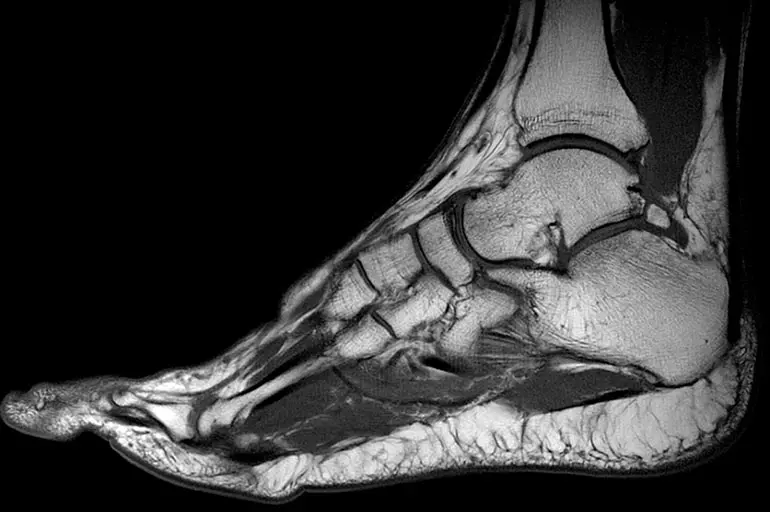

Це – сучасний спосіб діагностики, при якому застосовуються радіохвилі та магнітне поле. Іонізуюче випромінювання, на відміну від рентгенографії, не використовується. Тому МРТ безпечне і може призначатися необмежену кількість разів. Процедура відноситься до високоінформативних методів діагностики, особливо ефективних для дослідження м’яких тканин. МРТ допомагає отримувати зображення зрізів того чи іншого органу.

Нюанси розшифровки серії знімків

Після завершення процедури пацієнт отримує низку зображень у цифровій формі з описом виявлених патологічних змін. Також дається висновок із рекомендаціями для подальшого лікування та обстеження. У клініці «Меддіагностика» можна отримати повторний незалежний опис. Приклад висновку МРТ гомілкостопу:

- На серії знімків пропорції суглоба не змінено.

- Кості, що утворюють гомілковостоп, мають стандартну будову, правильне розташування. Виїмка кісточки розвинена нормально.

- Хрящові тканини таранного, гомілковостопного суглобів незначно витончені, відстань між кістковими поверхнями не змінена.

- У передньозовнішній області великогомілкової кістки виявлені ділянки помірного локального набряку.

- Суглобова оболонка потовщена.

- Виявляється збільшення інтенсивності сигналу в області таранно-малогомілкового сухожилля. Виявляються ознаки часткового ураження жирової тканини у прилеглих відділах. Ознаки розриву інших зв’язок відсутні. Між кісткові тканини інтактні.

- Будова ахіллового сухожилля не порушена. У нижніх відділах виявляється слабовиражене посилення сигналу. Загальний натяг сухожилля не порушено. Навколишні тканини в межах норми.

- Апоневроз підошви особливостей немає.

- Змін у параартикулярних тканинах не виявлено.

- Визначається незначна кількість рідини в ділянці гомілкостопу.

- Висновок: МР-симптоми артрозу таранного та гомілковостопного суглоба 2 ступеня, пошкодження малогомілкової зв’язки, ураження сухожилля п’яти. Випіт у синовіальній порожнині.

Самостійно розшифрувати знімки складно. Тому висновок потрібно передати лікарю. Лікар вивчає знімки, проводить повторний огляд, ставить діагноз.